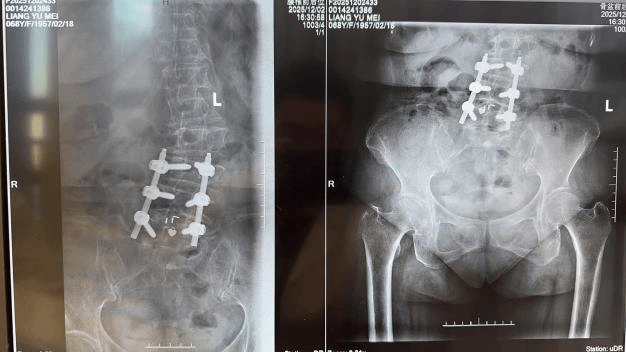

术前,团队借助影像学精准定位疼痛靶点,制定了个性化手术规划。术中在局部麻醉下,仅通过两个不足0.5厘米的微小切口,将电极精准植入脊髓硬膜外腔。手术全程耗时约1小时,通过实时神经电生理监测与患者术中反馈,确保电极位置精准无误,避免损伤周围神经血管。

术后,患者即刻反馈腰痛与右下肢疼痛明显缓解,困扰她一年多的顽痛大幅减轻。在医护人员指导下,患者当天即可下地行走,且行走姿态恢复正常,彻底摆脱了疼痛的束缚。目前,患者恢复良好,疼痛评分已降至正常范围,正在进行后续康复随访。